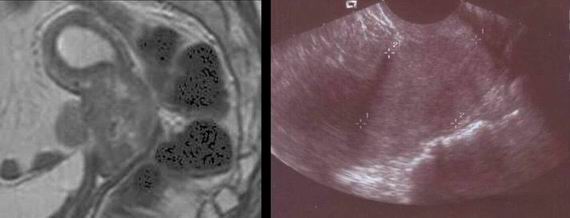

- Zobrazovací metody: US diagnostika Senzitivita: 87 %, specificita: 67 % Ferrazi,1997, grey scale US, Doppler US ( 0.4 RI: 100 % senz. 96-99% spec.), jiné zobrazovací metody (nemá lepší výsledky), MRI, CT, PET…

U nádorů LMP: (morfologie, flow, CA 125 )